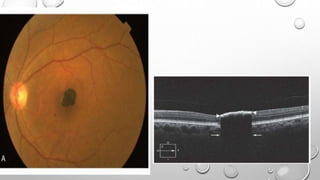

MACULAR HOLE

• 0- PERIFOVEOLAR DETACHMENT

• 1A- IMPENDING MACULAR HOLE

• 1B- OCCULT MACULAR HOLE

• 2- EARLY FTMH(PARTIAL OPENING OF

THE ROOF OF THE CYST)

• 3- ESTABLISHED FTMH

• 4- FTMH WITH PVD